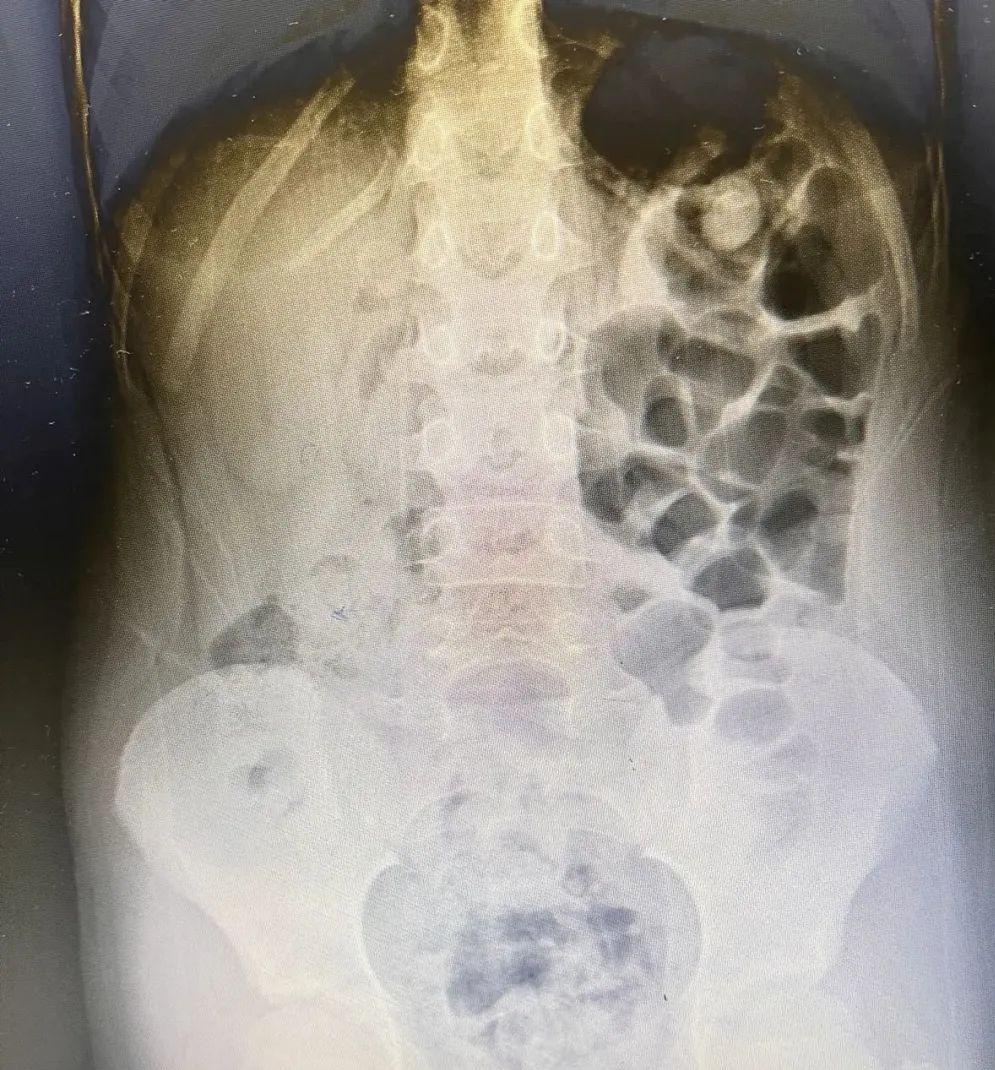

我仔细查体,也没有发现病理性便秘的高危因素。但是我还是明确一下是否有大便潴留的证据,拍了腹部立位片。(直肠内有明显大便潴留,结肠肠腔气体很多)。